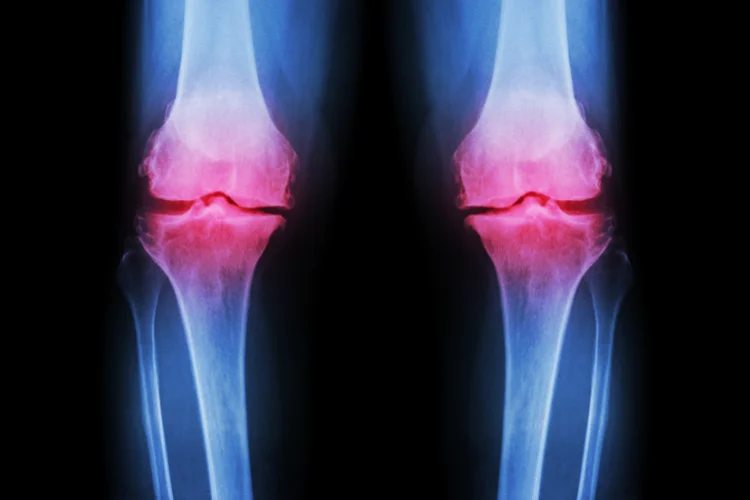

Cartilage repair refers to a range of medical procedures designed to address damaged

cartilage, the smooth tissue that cushions the ends of bones in joints and

allows them to move freely.

Cartilage can become damaged due to injury, repetitive stress,

or degenerative conditions such as osteoarthritis. This damage often results in pain,

stiffness, and reduced mobility in the affected joint.